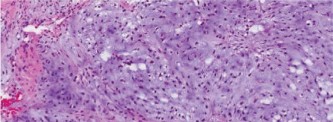

Which of the following histopathologic slides (Fig. 8–24A–D) is most consistent with osteosarcoma?

Figure 8–24 A–B

The correct answer is slide (D). Histologic examination of osteosarcoma reveals “lace-like” pink osteoid formed by malignant osteosarcoma cells. The degree of pleomorphism and atypia is considerable. Areas of necrosis with few viable cells (if any) are often seen.